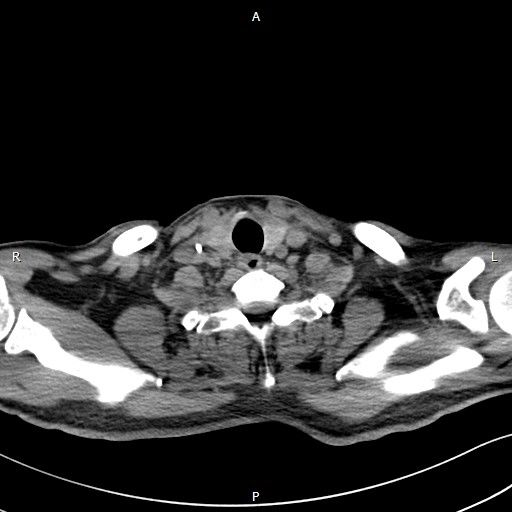

术后残余食管

11月6日,手术在全麻状态下进行。患者采取侧卧位,从左侧腋下开口约10厘米。李简教授在助手协同下,成功切除食管肿物,提拉胃部,将食管上部与胃进行充分吻合,并将肿瘤及周围淋巴结一一清除,有效降低食管癌术后并发症。手术涉及腹、胸、颈3个部位,历时5个小时,出血量100ml。术后3天患者已能下床活动,目前,孙叔叔恢复情况良好,可进流食。